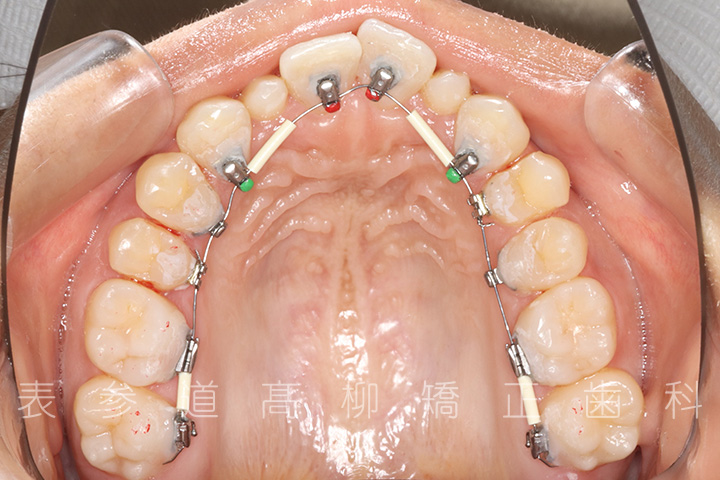

・上顎左側第一小臼歯、右側第二小臼歯を抜歯

・歯科矯正用アンカースクリューを併用し、前歯部を後方へ移動する

・上下歯列の緊密な咬合関係の確立に顎間ゴムを併用(装着時間20時間以上/日)

治療に用いた主な装置

・リンガルブラケット装置

・歯科矯正用アンカースクリュー

・アライナー